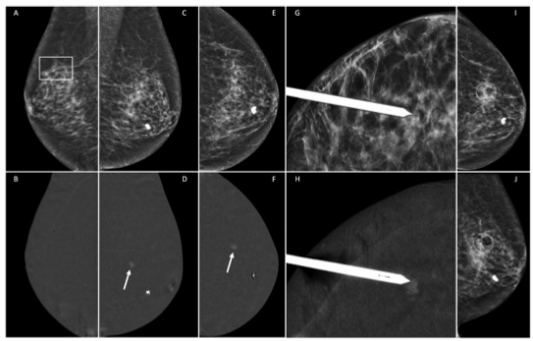

圖 一位無癥狀的77歲患者,有右側(cè)保乳手術(shù)史,在常規(guī)體外中心超聲檢查中發(fā)現(xiàn)可疑病灶后轉(zhuǎn)來進行補充評估(圖像不詳)。右側(cè)乳腺的低能量CEM MLO視圖(A)顯示與手術(shù)后疤痕有關的結(jié)構(gòu)變形(矩形),重組圖像(B)上沒有顯示異常增強病變。左側(cè)乳腺重組圖像(D和F)顯示了一個偶然發(fā)現(xiàn)的7毫米增強腫塊(箭頭),在低能量圖像(分別為C和E)或超聲上未見顯示。進行了左乳CEM引導下的活檢(G和H)。放射性標志物的正確位置得到確認,通常的2個乳腺造影視圖(I和J)。病理報告:導管內(nèi)乳頭狀瘤